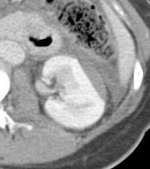

| Grade | Description | Image | CT |

| Grade | Type | Description |

| I | Contusion | Microscopic or gross hematuria. Urological studies normal. |

| I | Hematoma | Subcapsular, non-expanding without parenchymal laceration. |

| II | Hematoma | Non-expanding peri-renal hematoma confined to renal retroperitoneum. |

| II | Laceration | <1.0 cm parenchymal depth of renal cortex without urinary extravasation. |

| III | Laceration | >1.0 cm parenchymal depth of renal cortex without collecting system rupture or urinary extravasation. |

| IV | Laceration | Parenchymal laceration extending through renal cortex, medulla, and collecting system. |

| IV | Vascular | Main renal artery or vein injury with contained hemorrhage. |

| V | Laceration | Completely shattered kidney. |

| V | Vascular | Avulsion of renal hilum that devascularises kidney. |